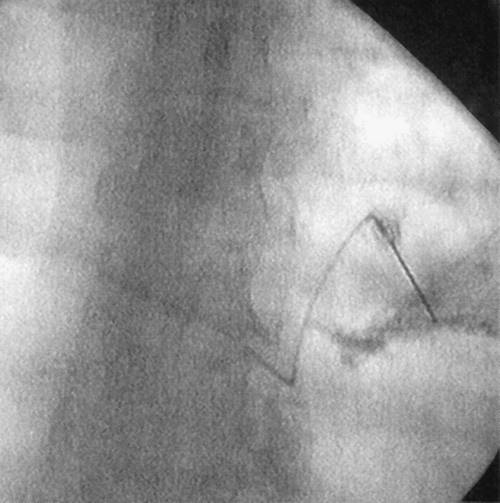

2. Use fluoroscopy whenever available to ascertain accuracy of needle placement and thus avoid pneumothorax.

Figure 20-3. Procedure done under fluoroscopy.

12. If the procedure is done under fluoroscopy, injection of 1 mL of contrast will confirm placement of the needle within the neurovascular space (Fig. 20-3).